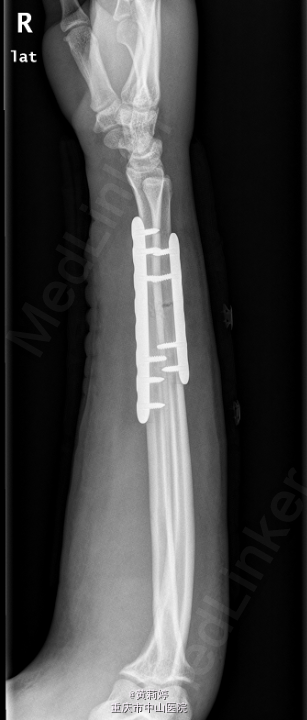

初步诊断: 右尺桡骨远端骨折. 麻醉下行“右尺桡骨骨折切复内固定术”. 沿掌侧肱桡肌内侧切开皮肤,长约15cm,暴露肱桡骨以及桡侧腕屈肌间隙分离桡动脉和桡神经间隙分离,见右桡骨中下段骨折,复位骨折端,放置8孔锁定钢板,予以近远端各打入三枚锁钉螺钉,C臂机透视见骨折位置好,螺钉位置可. 再沿尺骨背侧做一约10cm手术切口,逐层切开皮肤皮下组织,暴露尺骨骨折端,见尺骨骨折错位,予复位钳复位,放置6孔锁定钢板,近端远端各予两枚锁钉固定,C臂机透视见骨折位置好,螺钉位置可.

术后予安可欣1.5g静滴bid预防感染,指导患者术后早期功能锻炼等对症支持处理。